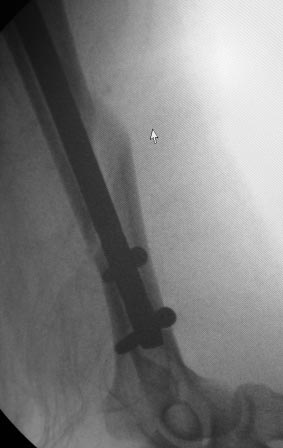

Операция 16.03.17г. БИОС закрытым способом СhM под ЭОП.В ходе рассверливания к/м канала дистального отломка, видимо, имеющийся осколок откололся , но стояние было удовлетворительное, в конце операции при контрольной проверке под ЭОП все было нормально (см.снимки под ЭОП).

На контрольной Р-грамме на следующий день – осколок сместился. Коллеги рекомендуют или щилом втолкнуть, или маленьким разрезом открыть и репонировать, и т.д.

по поводу "противных рентгенологов"))... на снимках ЭОП и R-грамм разница в проекциях градусов 30!..Ну , а если осколок так легко "гуляет",то плечо навряд ли простит такое,не?